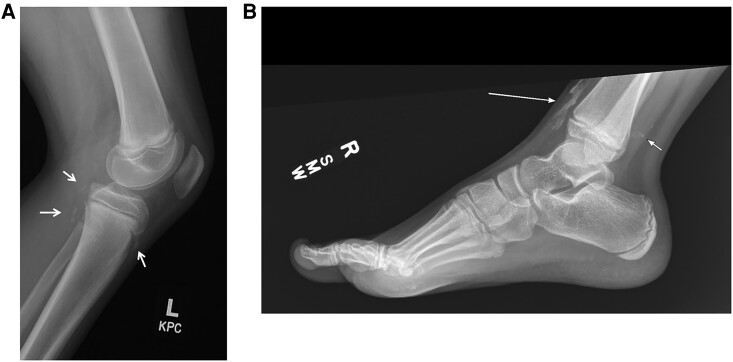

Progressive osseous heteroplasia (POH) is a rare autosomal-dominant hereditary bone disorder caused by inactivating pathogenic variants in GNAS1. POH is characterized by progressive cutaneous ossification and heterotopic ossification in skeletal muscles and subdermal connective tissues. Understanding of the natural history and phenotypic heterogeneity of the illness is incomplete. We report 2 affected male subjects with a milder than usual clinical course, highlight their clinical presentations and molecular correlates, and propose sodium 18F-fluorine positron emission tomography (PET) scanning as a sensitive technique for POH diagnosis and management.